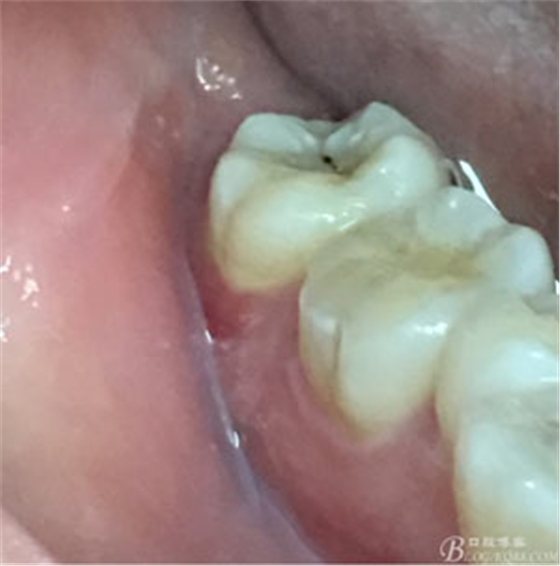

圖1.患者自述右側(cè)下后牙牙齦紅腫,咀嚼不適。術(shù)前口內(nèi)像:37頰側(cè)牙齦紅腫